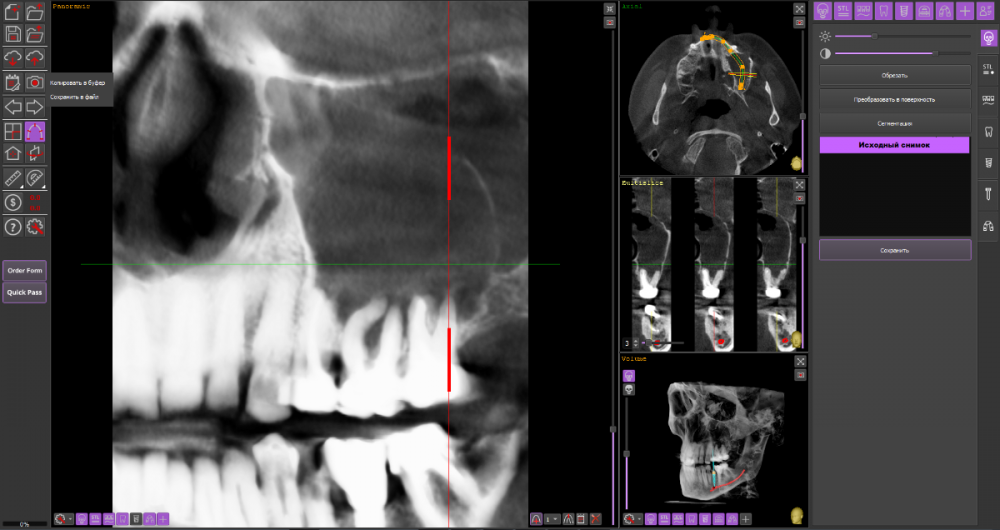

wladdX Опубликовано 22 марта, 2021 Поделиться Опубликовано 22 марта, 2021 При изучении КЛКТ, сделанной по другому поводу, обнаружил радикулярную кисту с врастанием в в/чел синус, размерами около 3*3*3см. Костных стенок кроме нижней и медиальной уже нет. Скрытый текст Как к этому делу подступиться правильно? Ссылка на комментарий

wladdX Опубликовано 23 марта, 2021 Автор Поделиться Опубликовано 23 марта, 2021 (изменено) Основная сложность, как мне кажется, отделить оболочку кисты от слизистой оболочки синуса. Может предварительно (за несколько дней?) провести декомпрессию? Изменено 23 марта, 2021 пользователем wladdX Ссылка на комментарий

wladdX Опубликовано 24 марта, 2021 Автор Поделиться Опубликовано 24 марта, 2021 (изменено) Найдены старые КТ, посмотрел: виновники 26 и 27 в равных долях. 25 включен позже, к\каналы у него обтурированы хорошо, прослеживаются остатки периодонта, при операции посмотрю на него из полости кисты Изменено 24 марта, 2021 пользователем wladdX Ссылка на комментарий